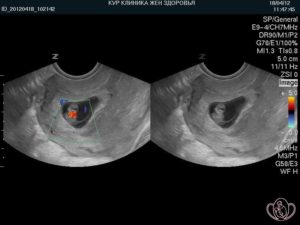

Итак, с шестой недели беременности можно увидеть и измерить биение на экране монитора. Прослушивается сердцебиение плода уже с пятой недели, особенно если УЗ-оборудование имеет хорошую мощность.

Трансвагинальный датчик обнаруживает сердечную деятельность с пятой недели, трансабдоминальный – не ранее, чем с шестой.

Если исследование делать трансвагинальным датчиком, то работу сердца эмбриона можно услышать уже на 5-6 неделе гестации. При проведении трансабдоминального УЗИ обнаружить пульсирующее сердце плода можно на 6-7 неделе. Более достоверная информация о характере и ритме сердцебиения дается трансвагинальным УЗИ.